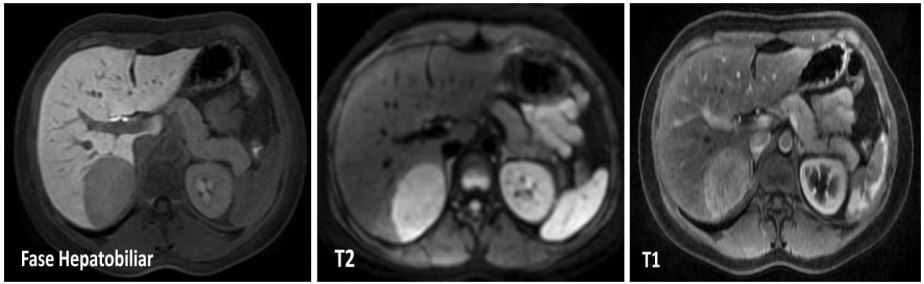

Frente a este quadro, é solicitada ressonância magnética nuclear de abdome com contraste hepatobiliar especifico (PrimovistR ), com as seguintes imagens:

Qual o diagnóstico e a conduta?